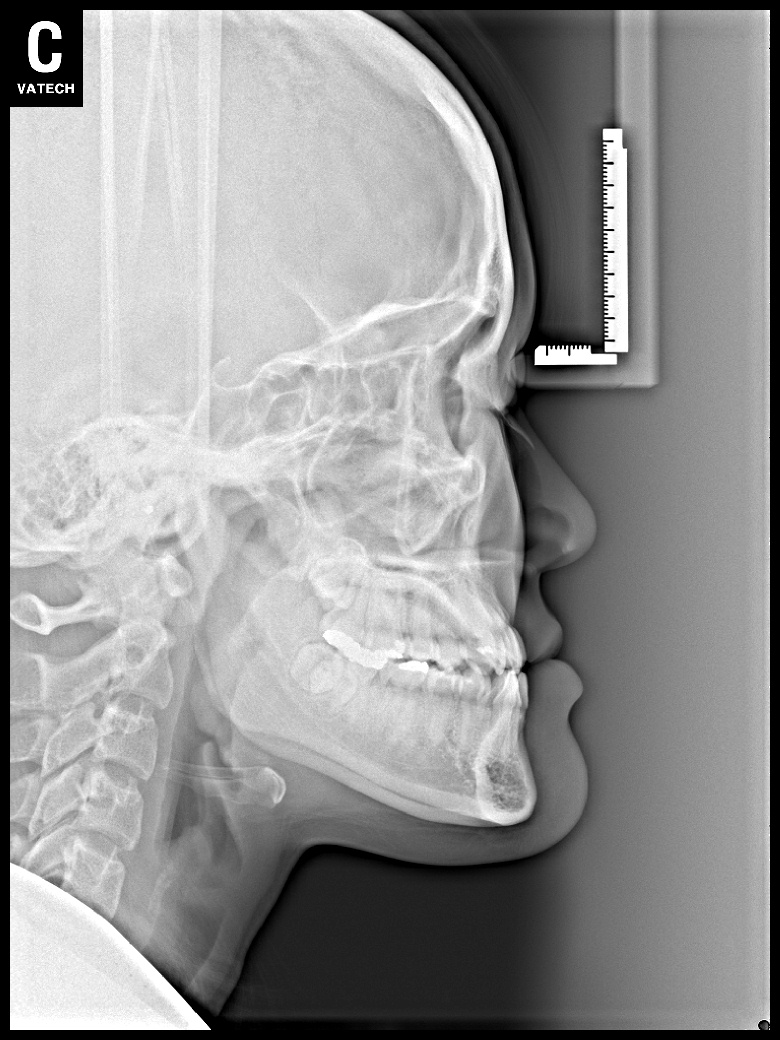

치료 전 사진입니다.